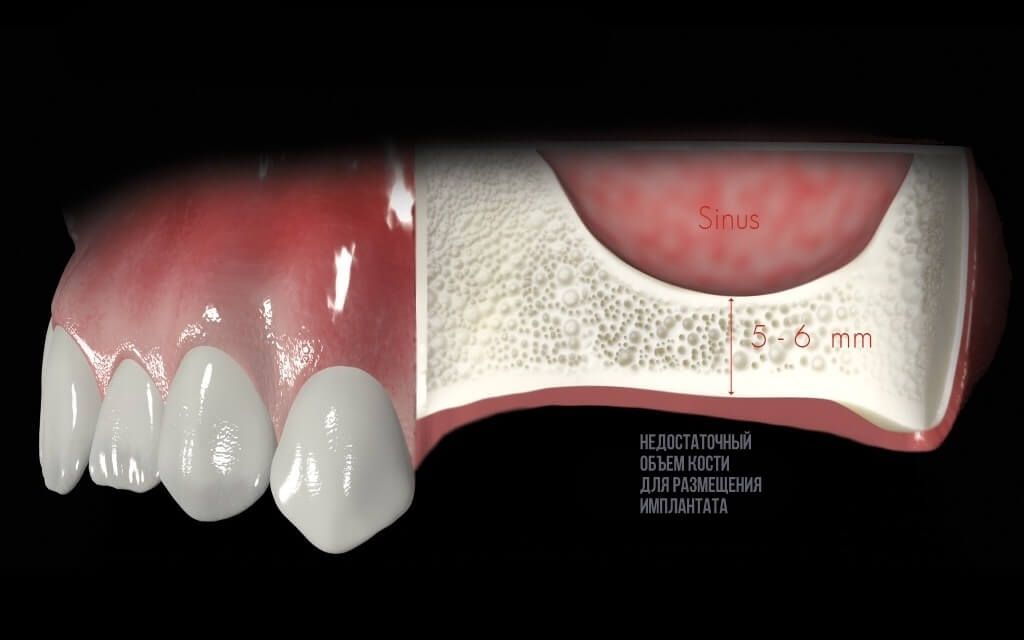

Синус лифтинг

После удаления зуба из-за отсутствия необходимой нагрузки на челюсть, кость в пустующем месте атрофируется. В этом случае перед имплантацией необходимо восполнить объем костной ткани.

Разновидность костной пластики направленной на увеличение объема костной ткани верхней челюсти в районе гайморовых пазух.

Открытый синус лифтинг

Открытый синус-лифтинг применяется, когда для установки имплантата не хватает более 3 мм костной ткани. При проведении этой операции имплантация в ряде случаев возможна только после полного восстановления кости челюсти.

Закрытый синус лифтинг

Закрытый синус-лифтинг подходит для наращивания небольшого объема костной ткани (1-3 мм). Он менее травматичен, чем открытый. Подсадка костного материала проводится через небольшое отверстие для имплантата.

При закрытом типе синус-лифтинга имплантация проводится сразу. Вам не придётся лишний раз посещать стоматолога.